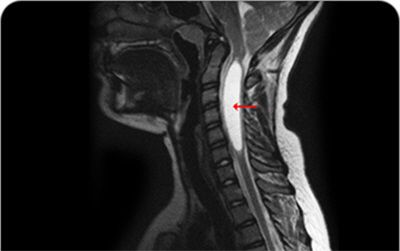

[이미지1] 척수공동증

/강남베드로병원

척수공동증을 그대로 방치할 경우, 심각한 척수 신경 손상으로 이어진다. 자기공명영상(MRI) 촬영, CT 촬영 등을 통해 척수 내 공동을 확인하고 근전도 검사, 신경전도 검사, 신경계의 이상 유무를 판별하는 유발전위 검사 등을 함께 시행한다. 필요시 뇌척수액 검사도 함께 시행한다.